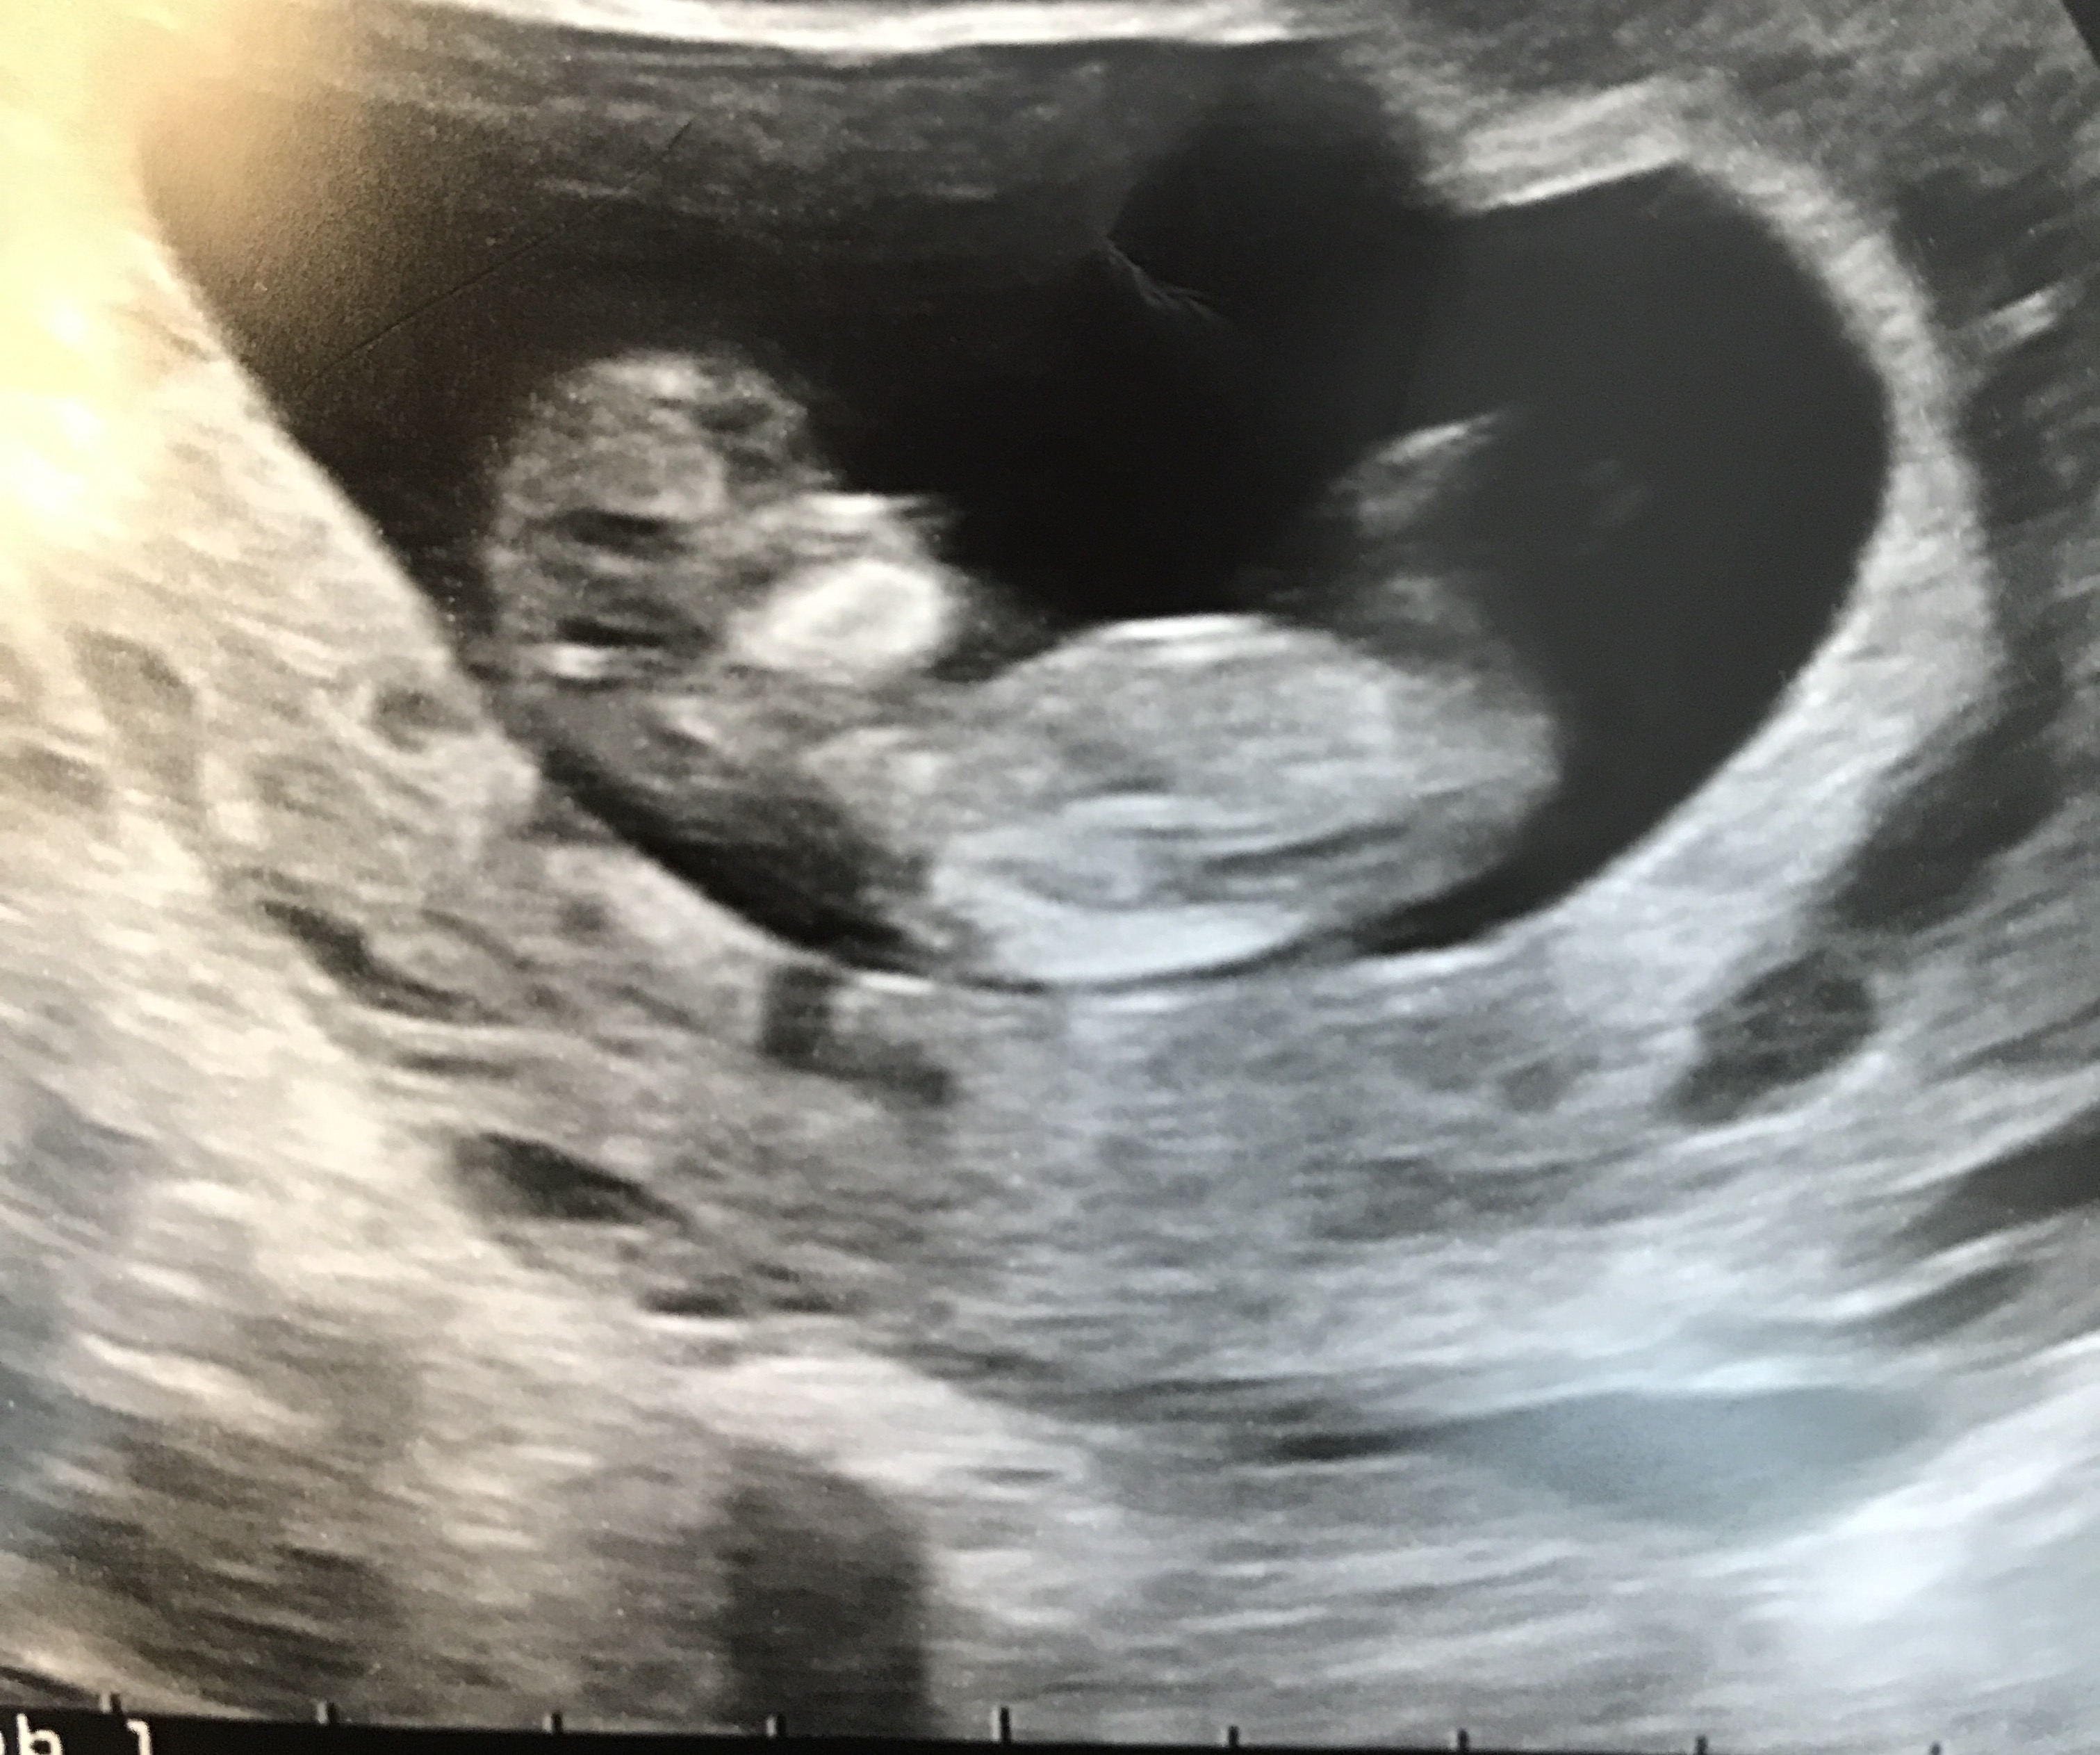

I was wondering if anybody can see the nub and can guess gender. I'm only 11.5 weeks but hoping if anyone can see anything 😊Attachment 36187Attachment 36188Attachment 36189

Hi everyone,

I just got my 13.3 week scan Hope to hear some guesses

Are these photos of a screen? do you happen to have a video you could post for us:) I am unable to zoom your current pictures at all so cannot make any guess atm.

No I don't have a video. When I zoom the pic in I can't upload them anymore. I will try it again